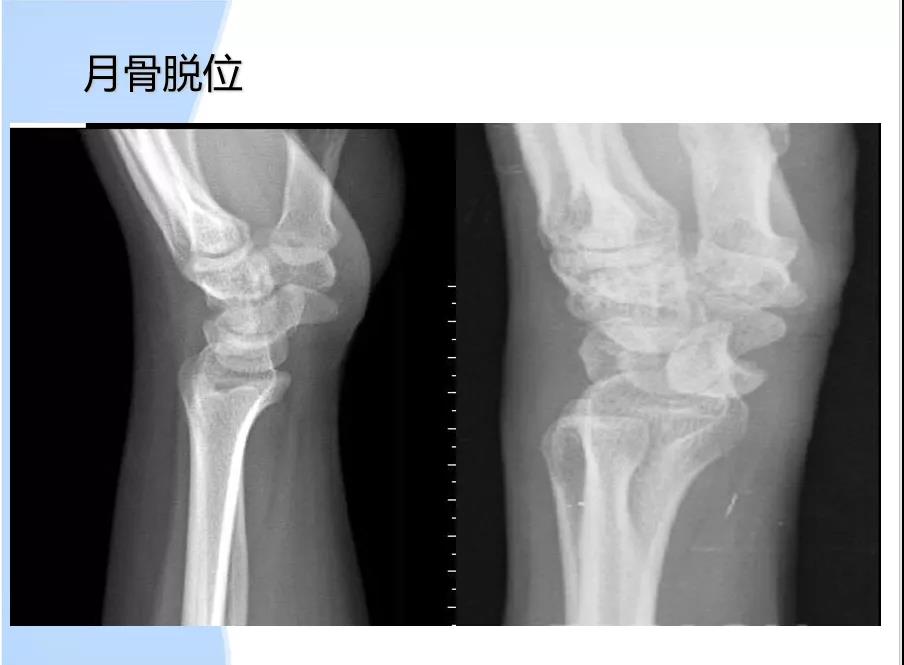

病因:1、腕管容量减小:月骨前脱位,腕部骨折(colles 反colles smith);腕和腕间关节增生性关节炎;腕横韧带增厚;感染或外伤致软组织水肿。2、腕管内容物增加:肿瘤(脂肪瘤、黄色瘤);腱鞘囊肿;腱鞘滑膜炎;3、解剖异常。4、正中动脉压迫。5、腕管内出血:外伤或血友病引发腕管内出血。6、其他:绝经;妊娠;痛风;类风湿;甲状腺功能低下。